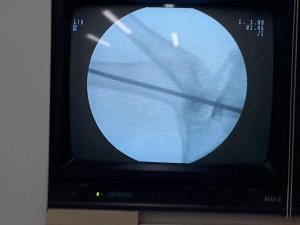

Como producto de una investigación interdisciplinar, un grupo de profesores y estudiantes de posgrado de la Universidad del Valle desarrollaron un nuevo cemento óseo, patentado por parte de la Superintendencia de Industria y Comercio.

“Kit de cemento óseo acrílico que comprende quitosano, óxido de grafeno, apatita, ácido poliláctico, cloruro de estroncio y comonomeros alcalinos” es el nombre de ésta nueva patente que le otorgaron a la Universidad del Valle.

El material cementante es utilizado en operaciones ortopédicas para fijar y pegar prótesis al hueso. Este desarrollo contó con el apoyo financiero del sistema general de regalías.

Las pruebas en humanos aún no se han realizado pues se esperan nuevos resultados con animales, para pasar a esta fase. Los cementos óseos son materiales empleados por cirujanos y ortopedistas para la fijación de prótesis articulares o dentales. Usualmente son dos componentes, una ampolleta de color oscuro y una bolsa estéril donde viene un componente sólido.

El cirujano mezcla ambos componentes y forma una pasta con la que impregna el hueso y la prótesis. El cemento endurece mediante una reacción de polimerización (exotérmica) que pega la prótesis al hueso.

Los cementos óseos convencionales que se encuentran en el mercado presentan algunas deficiencias en su aplicación como la generación excesiva de calor que puede quemar el tejido circundante y producir necrosis térmica de parte del hueso cementado.

También se pueden presentar problemas con el monómero o materia prima básica del material cementante que no alcanza a polimenizar y puede generar necrosis química. Otro problema que presenta este tipo de procedimiento es la presencia de infecciones por bacterias. Todos estos inconvenientes disminuyen el tiempo de fijación hueso-prótesis, que en procedimientos satisfactorios varía entre 7 y 10 años.

-Se cambiaron los componentes como el cloruro de circonio que sirven para visualizar el pegante en una radiografía, por materiales que son mejor asimilados por el cuerpo.